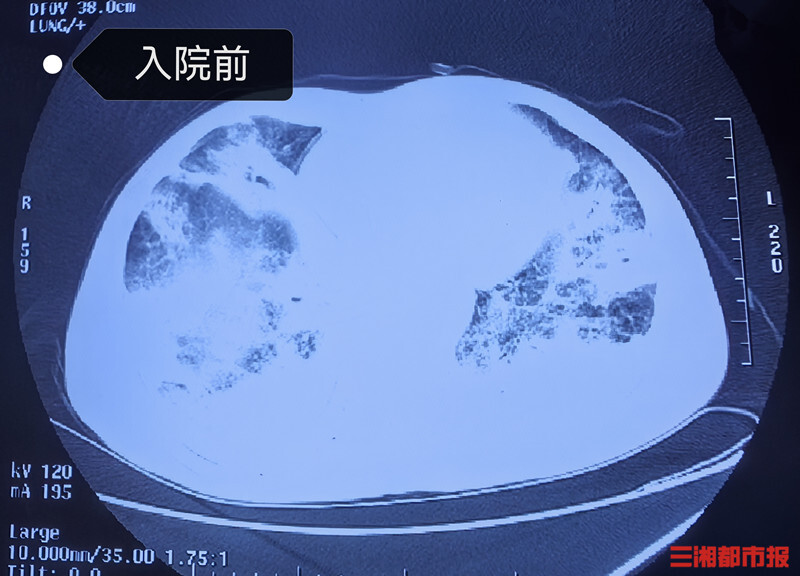

没想到1周后,姚大爷咳嗽、咳痰症状逐渐加重,并出现发烧、呼吸困难等症状,这才到医院就诊,然而辗转多家医院,病情未得到很好的控制,反而逐渐加重,为求进一步治疗,转至湖南省人民医院呼吸三病区(RICU)。

科室主任李建民带领团队立即为姚大爷在科内组织疑难病例讨论,经过仔细询问病史及分析病情。经肺泡灌洗液的病原学检查,在其肺内找到了烟曲霉菌(真菌的一种)、肺炎链球菌(社区获得性肺炎的常见细菌)等病原体混合感染。

通过治疗,姚大爷最终转危为安。一段时间后续治疗后,2月5日,姚大爷身体达到出院条件,待雨雪冰冻天气情况好转后返乡过年。